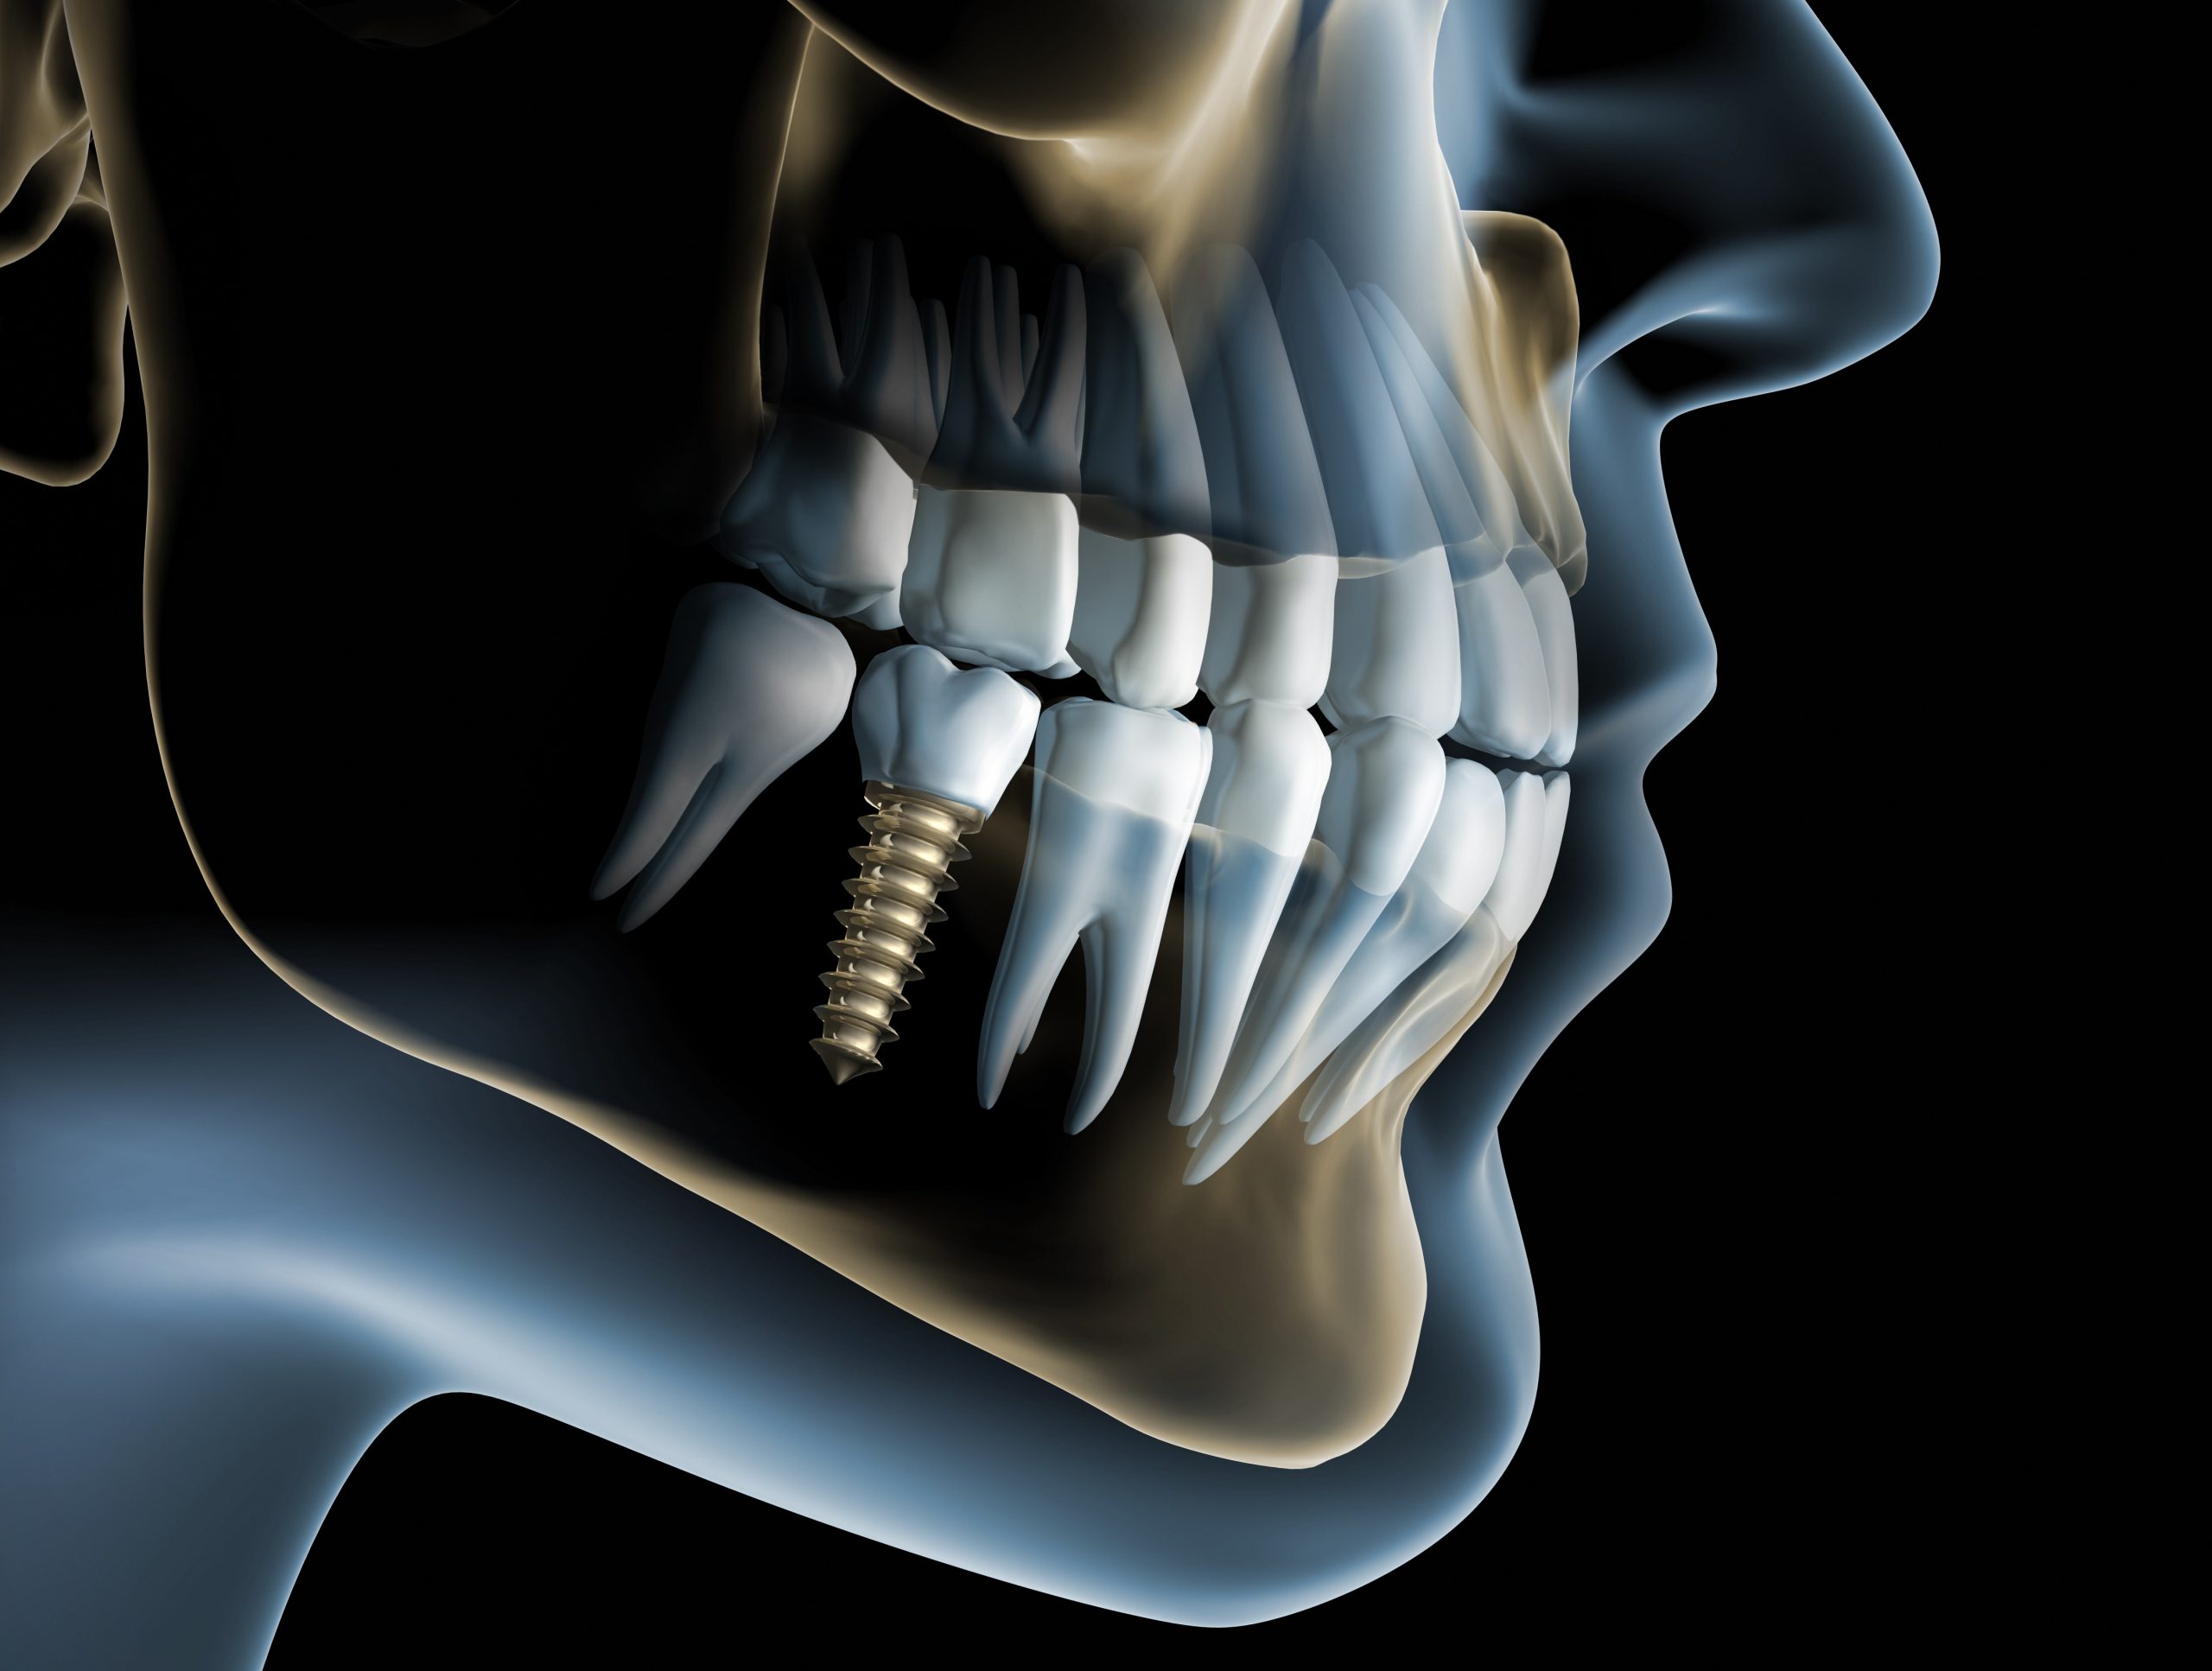

歯を失うのは、虫歯や歯周病の重症化だけではありません。スポーツや交通事故などで顔面を強打した際に歯が折れる・歯が抜けることも多々あります。今回はそんな外傷によって歯を失った場合のインプラント治療についてわかりやすく解説します。

歯を失うのは、虫歯や歯周病の重症化だけではありません。スポーツや交通事故などで顔面を強打した際に歯が折れる・歯が抜けることも多々あります。今回はそんな外傷によって歯を失った場合のインプラント治療についてわかりやすく解説します。

外傷によって歯を失った場合は、受傷した部位がどのようになっているかでインプラント治療のプロセスも変わってきます。具体的には、損傷したのは歯だけなのか、あるいは顎の骨も一部欠けたり、折れたりしているのかによって行うべき処置が異なります。

外傷によって歯のみ失ったケースは、比較的治療が進めやすいです。というのもインプラント治療では、チタン製の人工歯根を埋め込むことから、顎の骨の状態が何より重要となります。受傷した部位の顎骨が無傷であれば、とくに配慮することなくインプラント治療を進められます。もちろん、外傷を負った歯が折れて歯根が一部残っているような場合は、抜歯も行わなければなりません。

転倒などで顔面に強い衝撃を受けると、歯だけでなく顎の骨まで折れることも珍しくありません。重症例では折れた顎の骨が大きくズレたり、広範囲に顎骨を失ったりします。いずれもすぐにインプラント治療を開始するのは不可能です。まずは、顎の骨の治療を優先します。ズレた骨は整復処置を施し、欠損した部分は骨移植を実施します。そうして顎の骨の状態が良好になったら、インプラント治療を開始します。外傷後の骨移植を行うようなケースでは、6~12ヶ月程度、治癒期間を設ける必要があります。

外傷によって失った骨は、GBR法やブロック骨移植などで補います。GBRは通常のインプラント治療でもよく行われる治療法で、骨が欠損した部位に患者さまご自身の骨(自家骨)や人工骨を移植して再生をはかります。ブロック骨移植は、欠損が比較的大きい場合に適応される外科処置で、患者さまご自身の骨をブロック状で削り出し、欠損部に移植する方法です。移植骨は下顎の親知らずや前歯の周囲から削り出します。

外傷によって失った骨は、GBR法やブロック骨移植などで補います。GBRは通常のインプラント治療でもよく行われる治療法で、骨が欠損した部位に患者さまご自身の骨(自家骨)や人工骨を移植して再生をはかります。ブロック骨移植は、欠損が比較的大きい場合に適応される外科処置で、患者さまご自身の骨をブロック状で削り出し、欠損部に移植する方法です。移植骨は下顎の親知らずや前歯の周囲から削り出します。